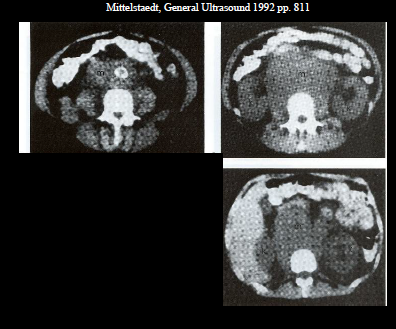

what are these examples of?

peripancreatic lymph nodes (pt has history of lymphoma)

same below

paraortic lymph nodes (pt has history of AIDS)